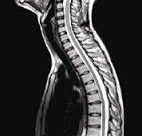

MRI עמוד שדרה צווארי (MRI C-Spine) היא בדיקה בטוחה וללא כאבים אשר נועדה להדגים את המבנה של עמוד השדרה הצווארי. בבדיקה ניתן גם לסקור את הצוואר עצמו ואת הרקמות הרכות הנמצאות בו (אם כי יש לכך בדיקה מיוחדת אשר נקראת MRI צוואר רקמות רכות). בדיקת MRI עמוד שדרה לאזור הצוואר מצוינת להדגמת בלטים ופריצות דיסק. כמעט כל … המשך לקרוא MRI עמוד שדרה צווארי